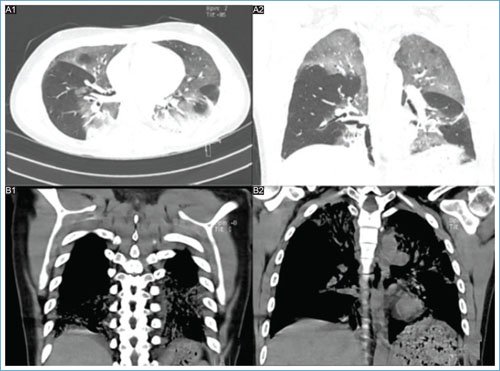

A lo largo de su estancia hospitalaria presentó elevación progresiva de azoados, con creatinina y nitrógeno ureico en sangre elevados, evidenciando falla renal con indicaciones de hemodiálisis. Las imágenes radiológicas iniciales no mostraron alteraciones respiratorias; sin embargo, en estudios posteriores se evidenció una alteración de la morfología pulmonar con atelectasias laminares basales bilaterales, engrosamiento peribronquial central y opacidades irregulares basales izquierdas sugestivas de ocupación alveolar (Fig. 1). La tomografía computarizada mostró consolidaciones parenquimatosas en las bases pulmonares con broncograma aéreo y opacidades alveolares con patrón de vidrio esmerilado en los lóbulos superiores, el lóbulo medio y la língula, lo que sugiere un proceso inflamatorio pulmonar (Fig. 2).

Figura 2. Hallazgos tomográficos. A (1-2): consolidaciones parenquimatosas en las bases pulmonares con broncograma aéreo; opacidades alveolares con patrón de vidrio esmerilado en los lóbulos superiores, el lóbulo medio y la língula, que sugiere compromiso inflamatorio; considerar neumonía multilobar. B (1-2): hallazgos en el parénquima pulmonar que sugieren cambios por un proceso de tipo neumónico multilobar; correlacionar con antecedentes.